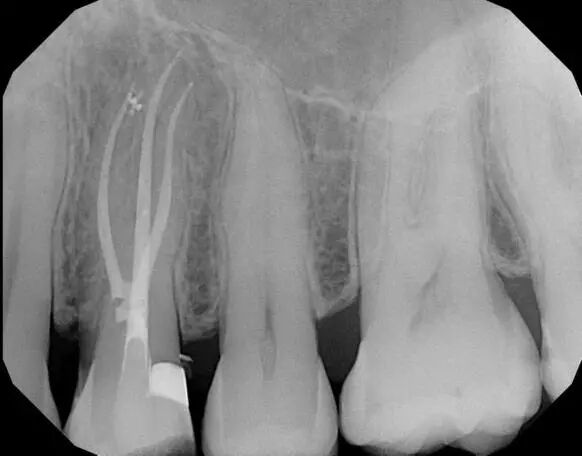

热凝牙胶根管充填技术是利用牙胶加热软化后具有流动性的特点,实现了根管的三维充填,使根管充填的效果更理想。它是目前国际认可的最佳根管治疗充填技术。

一是精确度高,可达根尖0.5mm左右;

三是封闭性好,尤其适用于狭窄弯曲和形态复杂的根管治疗,防止再次感染;

四是稳定性强,可塑性佳,便于进一步治疗。